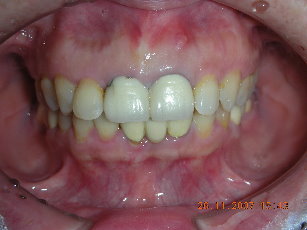

全瓷冠-上顎門牙不密合假牙

審美牙科

全瓷冠